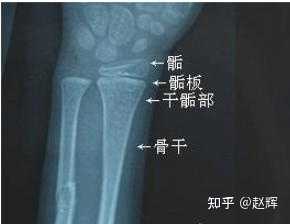

人不是任何时候想长高就能长高。大多数人18岁以前骨骺线就闭合了,有些人是晚长体质,也许20多岁骨骺线还没闭合,就还能长(比如张继科)。

但是归根结底,骨骺线闭合后就不能长高了。文字游戏不好玩,混淆概念只会让真想长高的人误解,用错方法。

我可以很负责任地说:只要没闭合,就还能长高。但是每个人骨骺线闭合的时间不一样,有可能他16岁就闭合了,你26岁还没闭合,然后一年长高了3厘米。

拍骨骺线也比较简单,到正规医院花一两百块钱拍个x光,还能不能长高,当场就能知道答案。